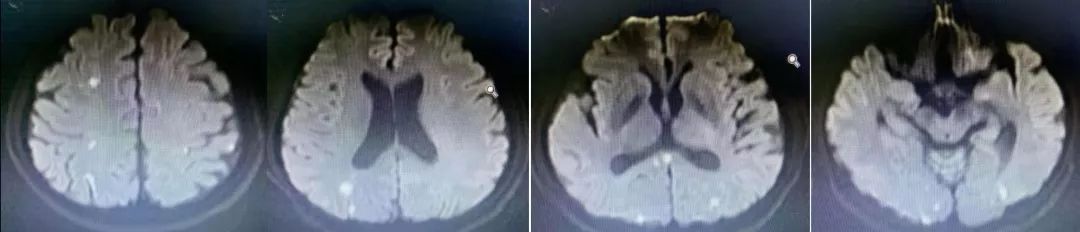

病例9

男性,62岁,因头痛,反应迟钝2月入院,既往有脑梗死病史。

答案:脑淀粉样血管病。

脑淀粉样血管病(Cerebral amyloid angiopathy,CAA)是一种以皮层和软脑膜血管壁内 β 淀粉样蛋白沉积(Amyloid-beta,Aβ)为特征的脑小血管疾病。CAA 是除高血压外,导致老年人脑出血的常见原因。CAA临床表现:脑叶出血,皮质微出血,皮质浅表含铁血黄素沉积/ 局灶性凸面蛛网膜下腔出血( SAH) ,皮层梗死和白质缺血性病变,痴呆,CAA相关炎症,淀粉样发作。淀粉样发作又称短暂性局灶性神经系统发作(transient focal neurological events,TFNE),作为无脑叶出血的脑淀粉样血管病患者的主要临床表现之一,与局灶皮质小灶出血有关,近年来已经逐渐被认为是CAA的另一个重要的临床特征。部分TFNE表现为"阴性"症状,如发作性的偏瘫或失语等,与经典的TIA发作极其类似,临床需要仔细鉴别。

CAA 的确诊只能基于脑血管中淀粉样蛋白沉积的活检证据。根据修改后的波士顿诊断标准,临床和影像学检查结果可以诊断出“可能CAA”。MRI的发展提高了我们检测“出血迹象” 的能力。当脑叶出现大量出血或微出血,其他原因被排除时,即使在没有组织病理学证实的情况下,也应归类为“可能 CAA”。